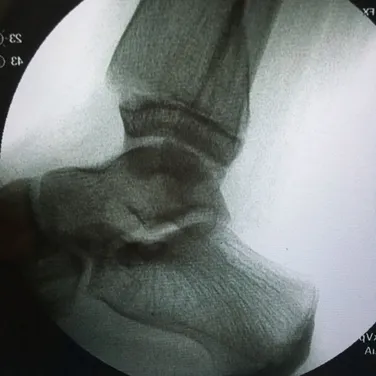

Nerves may be compressed from tight ligaments, inflamed tendons, tumors, fracture fragments, varicose veins, scar tissue or injuries to the foot that cause the foot and ankle to be misshapen (severe flatfoot).  Nerve compression may cause significant discomfort with weightbearing.  Night pain and pain while the patient is nonweightbearing are common as well.  The most important a physician can do is to direct the treatment to the cause of the problem.  If the foot is misshapen causing no pain (numbness, tingling or shooting), the nerve does not need surgery, the foot and ankle bones might.  The wrong diagnosis can be disastrous.  If a tumor or varicose vein is causing the pain they may need to be resected to allow the nerve to function normally.  Anything abnormally applying pressure to the nerve may cause symptoms.  If a tight ligament is identified, it has to be released to allow the nerve to function normally.  Occasionally nerve conduction studies are performed to assess the degree of nerve compression and nerve damage. The common peroneal nerve is located at the fibular neck, just to the outside of the knee.  If the nerve is injured or damaged, it can cause a dropfoot due to paralysis of the muscles that it innervates.

Nerves may be compressed from tight ligaments, inflamed tendons, tumors, fracture fragments, varicose veins, scar tissue or injuries to the foot that cause the foot and ankle to be misshapen (severe flatfoot).  Nerve compression may cause significant discomfort with weightbearing.  Night pain and pain while the patient is nonweightbearing are common as well.  The most important a physician can do is to direct the treatment to the cause of the problem.  If the foot is misshapen causing no pain (numbness, tingling or shooting), the nerve does not need surgery, the foot and ankle bones might.  The wrong diagnosis can be disastrous.  If a tumor or varicose vein is causing the pain they may need to be resected to allow the nerve to function normally.  Anything abnormally applying pressure to the nerve may cause symptoms.  If a tight ligament is identified, it has to be released to allow the nerve to function normally.  Occasionally nerve conduction studies are performed to assess the degree of nerve compression and nerve damage. The common peroneal nerve is located at the fibular neck, just to the outside of the knee.  If the nerve is injured or damaged, it can cause a dropfoot due to paralysis of the muscles that it innervates.  Nerves may be compressed from tight ligaments, inflamed tendons, tumors, fracture fragments, varicose veins, scar tissue or injuries to the foot that cause the foot and ankle to be misshapen (severe flatfoot).  Nerve compression may cause significant discomfort with weightbearing.  Night pain and pain while the patient is nonweightbearing are common as well.  The most important a physician can do is to direct the treatment to the cause of the problem.  If the foot is misshapen causing no pain (numbness, tingling or shooting), the nerve does not need surgery, the foot and ankle bones might.  The wrong diagnosis can be disastrous.  If a tumor or varicose vein is causing the pain they may need to be resected to allow the nerve to function normally.  Anything abnormally applying pressure to the nerve may cause symptoms.  If a tight ligament is identified, it has to be released to allow the nerve to function normally.  Occasionally nerve conduction studies are performed to assess the degree of nerve compression and nerve damage. The common peroneal nerve is located at the fibular neck, just to the outside of the knee.  If the nerve is injured or damaged, it can cause a dropfoot due to paralysis of the muscles that it innervates.